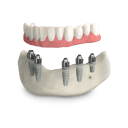

По уникальной методике

БЕЗ отёков и надрезов

Установка

за 1 день